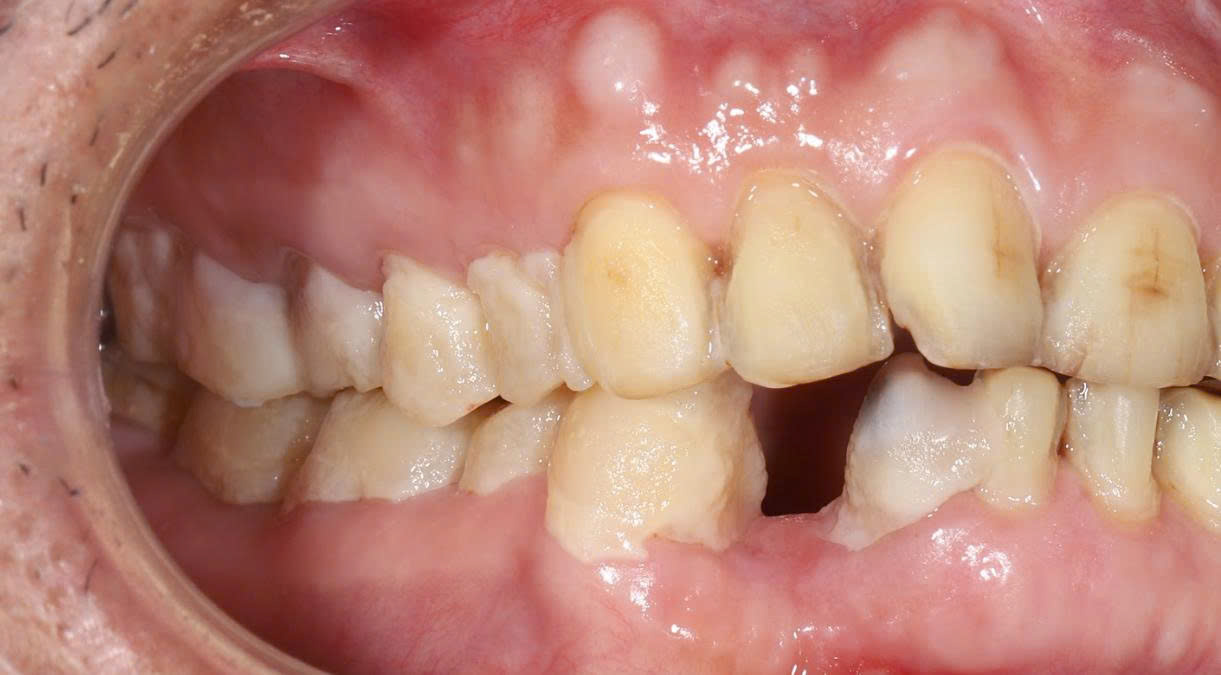

3.1 Khám trong miệng

-

Hầu hết các răng hai hàm đã bị mài nhỏ quá mức

Răng số 8 (răng khôn) bị mài và bọc sứ – hoàn toàn sai chỉ định

Viền lợi không đều, có dấu hiệu viêm quanh răng

Bệnh nhân phản ánh đau nhức âm ỉ kéo dài